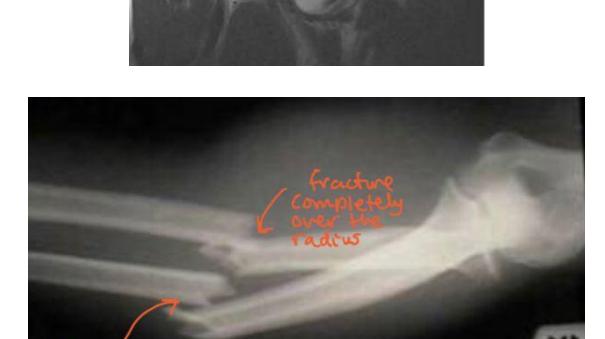

Monteggia Fracture

- Location: Proximal ulna fracture w/ radial head dislocation ย fracture of the proximal (or midโshaft) ulna with dislocation of the radial head at the elbow. ย